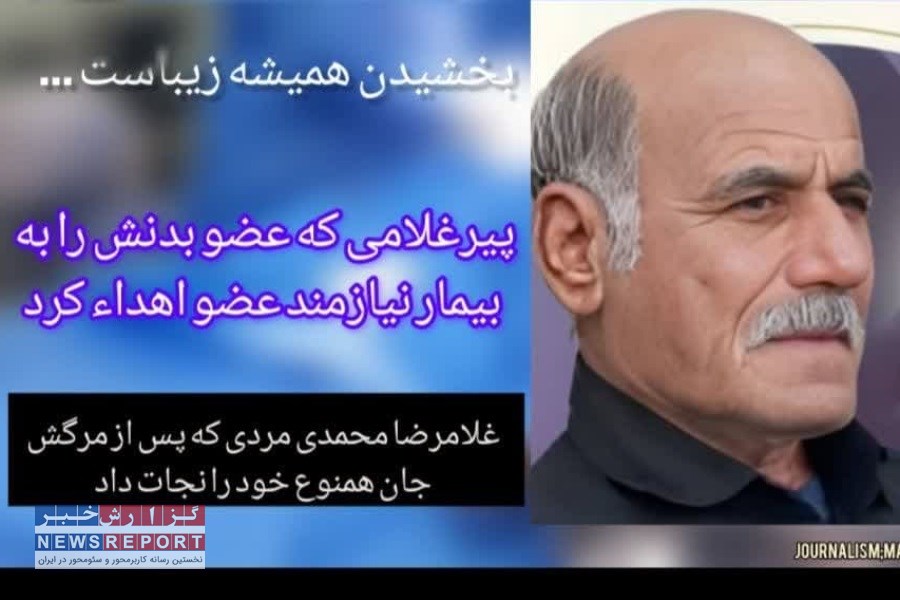

به گزارش خبرنگاران گروه جامعه خبرگزاری گزارش خبر، سیاوش غلامی مدیر واحد فراهم آوری و پیوند اعضای بیمارستان تخصصی و فوق تخصصی ابوعلی سینای شیراز در گفت وگو با محمود صابری زاده خبرنگار و دستیار رسانه ای در فارس اظهار کرد: با رضایت خانواده مهربان «حاج غلامرضا محمدی» مداح و ذاکر اهلبیت(ع) که به دنبال تصادف دچار مرگ مغزی شده بود، اعضای بدنش برای بیماران نیازمند پیوند برداشت شد.

وی تصریح کرد: تنها عضوی که از وی برداشت و قابل استفاده شده کبد ایشان بوده که این عمل برداشت عضو نیز، در بیمارستان حاج محمود حاج حیدر لامرد انجام گرفته است.

غلامی ضمن تشکر از خانواده این مرحوم که رضایت به اهدای اعضای آن عزیز برای بیماران نیازمندان به پیوند داده بودند از تمامی تلاشهای پرسنل و مدیریت بیمارستان حاج محمود حاج حیدر لامرد قدردانی کرد و گفت: این اولین برداشت عضو در سال ۱۴۰۴ در بیمارستان لامرد می باشد.

مسئول مرکز فراهم آوری اعضای پیوندی دانشگاه علوم پزشکی شیراز خاطرنشان کرد: این اقدام ارزشمند نشان از روح بزرگ و نوعدوستی دارد و الگویی برای ترویج فرهنگ اهدا عضو در جامعه است.

وی بیان کرد: این محب اهلبیت ۶۶ساله که دارای سه فرزند پسر و پنج فرزند دختر می باشد، پنج شنبه عصر در زادگاهش گلزار شهدای روستای غیب الهی علامرودشت به خاک سپرده شد.